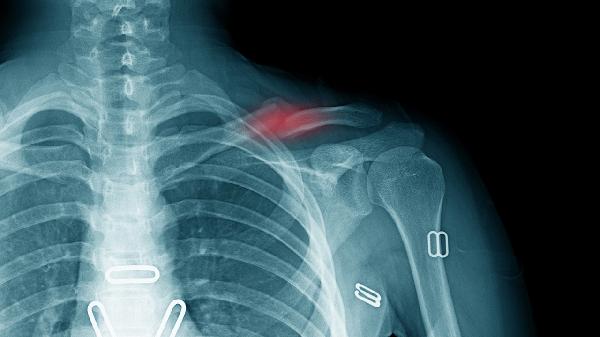

严重胸部撞击可能导致肋骨骨折畸形愈合,多根肋骨骨折可能引发连枷胸。急性期需固定胸壁,后期通过肋骨成形术恢复解剖结构,避免影响呼吸功能。